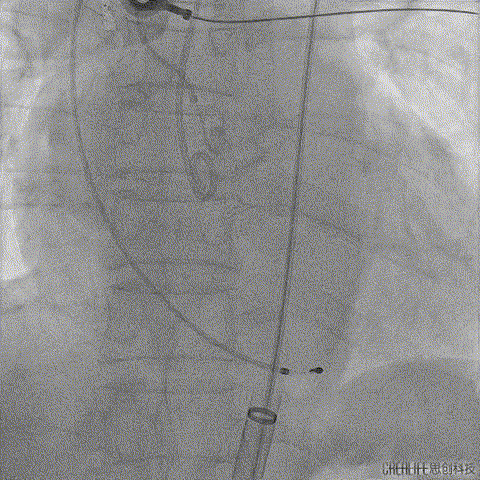

考虑到术中积极行冠脉保护,该手术从绕动脉穿刺造影指导左右股动脉穿刺;

经桡动脉穿刺造影指导左侧股动脉穿刺

经桡动脉穿刺造影指导右侧股动脉穿刺